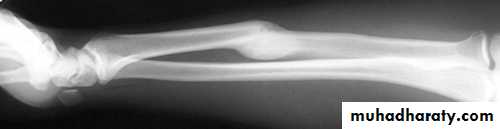

Ischemic contracture :

Following arterial injury or compartment syndrome, the patient may develop ischaemic contractures of the affected muscles (Volkmann’s ischaemic contracture).The sites most commonly affected are the forearm and hand, leg and foot.

Myositis ossificans :

Heterotopic ossification in the musclesCommon sites : elbow or a blow to the brachialis, deltoid or quadriceps. especially in unconscious or paraplegic patients

x-ray may show fluffy calcification in the soft tissues.

The joint should be rested in the position of function until pain subsides; gentle active movements are then begun.

Months later, when the condition has stabilized, it may be helpful to excise the bony mass.

Indomethacin or radiotherapy should be given to help prevent a recurrence.